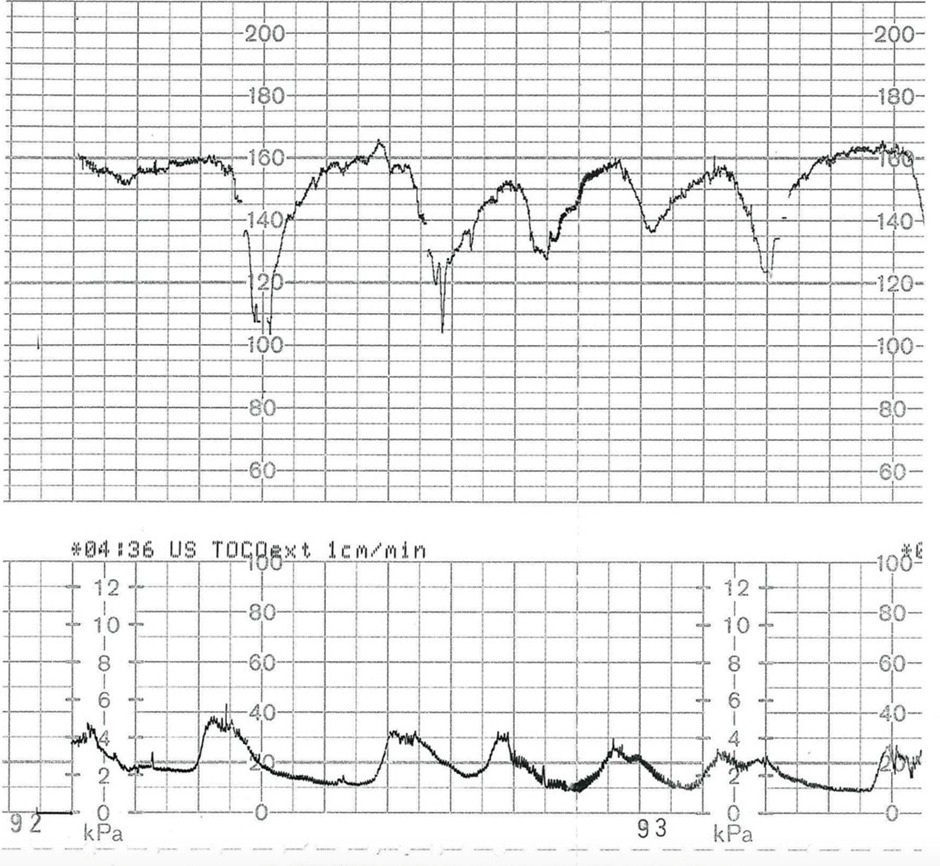

- Fetal distress (earliest and most sensitive sign)

- Sudden pause in contractions